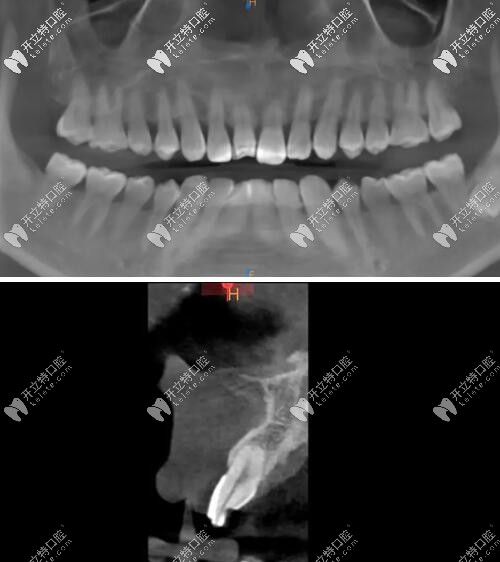

影像學(xué)檢查

門牙磕斷傷及牙根影像學(xué)檢查

被磕的牙冠根向折裂,直達(dá)骨下;

牙根骨量充足;

牙長(zhǎng)軸和牙槽骨的方向基本一致。